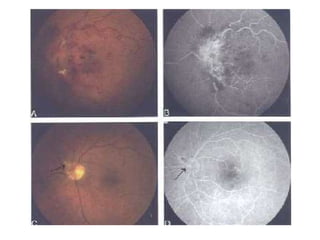

ICRVONICRVO